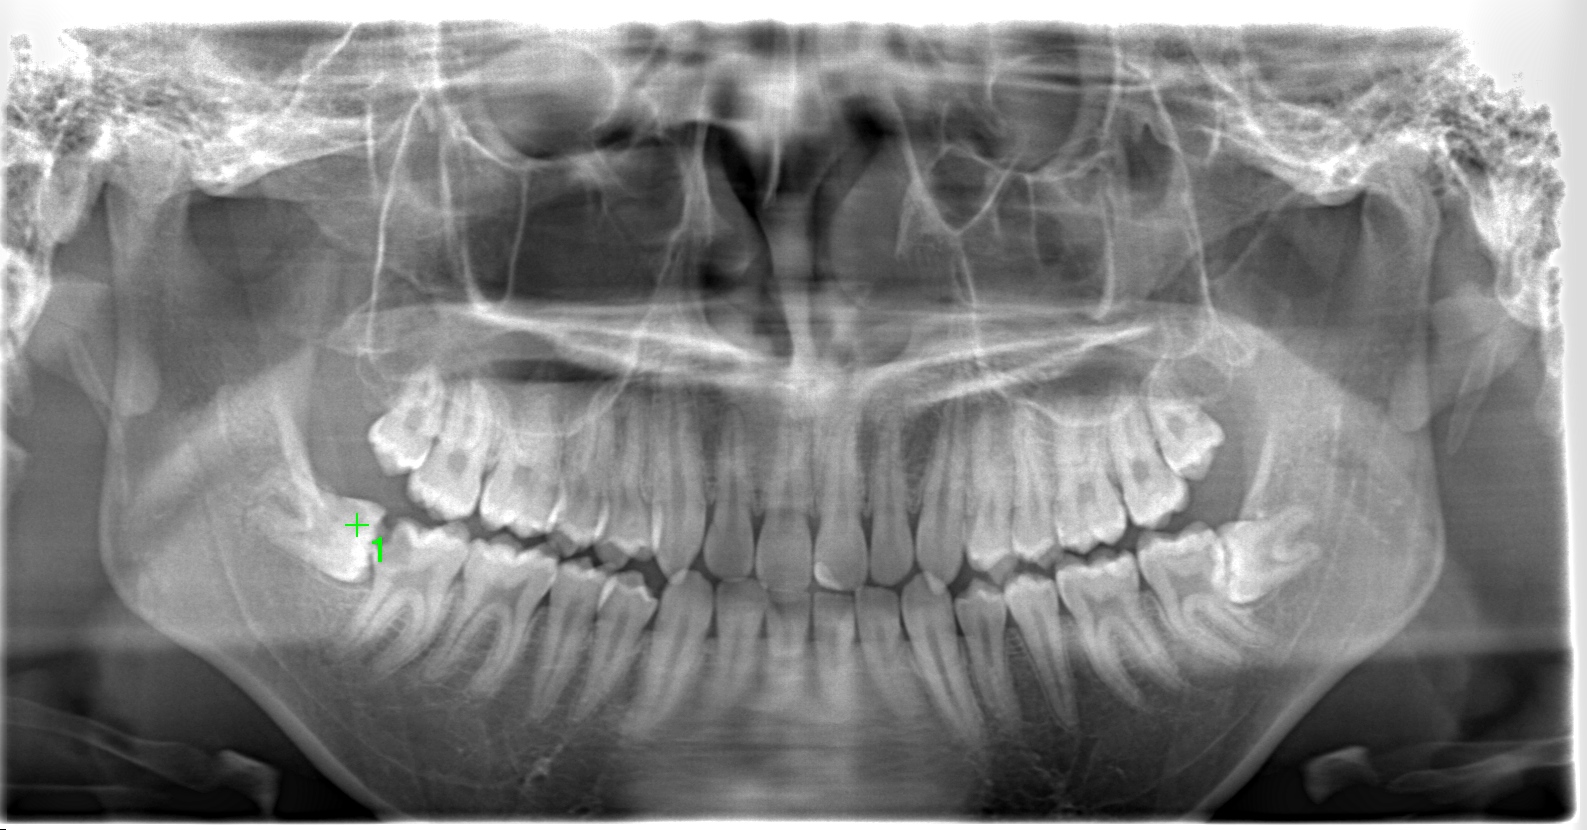

左下奥歯が腫れた 20代 男性 親知らずの抜歯

| 通院目的 | 右下の虫歯と親知らずの腫れ | ||

| 診断 | 虫歯と親知らずの炎症 | ||

親知らずが腫れている | ||

| 通院期間・回数 | 1週間・3回 | ||